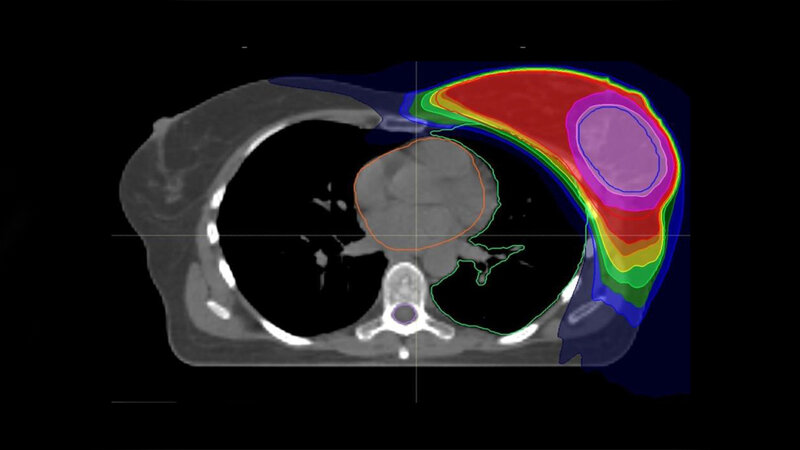

Die vom Bundesministerium für Bildung und Forschung geförderte Studie ist eine Kooperation der Universitätskliniken Heidelberg und Tübingen. An beiden Standorten wurden zwischen 2011 und 2015 insgesamt 502 Brustkrebs-Patientinnen nach brusterhaltender Operation und mit erhöhtem Risiko für ein Wiederauftreten des Tumors in die Studie eingeschlossen. Die Zuteilung zu den beiden Behandlungsgruppen erfolgte zufällig. Die aktuellen Leitlinien der Amerikanischen Gesellschaft für Radioonkologie (ASTRO) zur Strahlentherapie bei Brustkrebs empfehlen bislang noch die anschließende Boost-Bestrahlung. „Das liegt daran, dass es bisher noch keine belastbaren Daten zur Bewertung des integrierten Boosts gab“, so Professor Dr. Dr. Jürgen Debus, Ärztlicher Direktor der Radiologischen Universitätsklinik und Letztautor der Studie. „Unsere Ergebnisse sind ein erster wichtiger Schritt zur evidenzbasierten Aktualisierung der Leitlinien.“ Insbesondere moderne Bestrahlungstechniken wie die sogenannte Intensitätsmodulierte Radiotherapie (IMRT), bei der Risikoorgane bestmöglich geschont werden können, haben der neuen Entwicklung den Weg geebnet. Inwieweit sich die Ergebnisse auf die seit rund drei Jahren zunehmend angewandte, verkürzte Radiotherapie der Brust übertragen lassen, ist Gegenstand aktueller Studien.